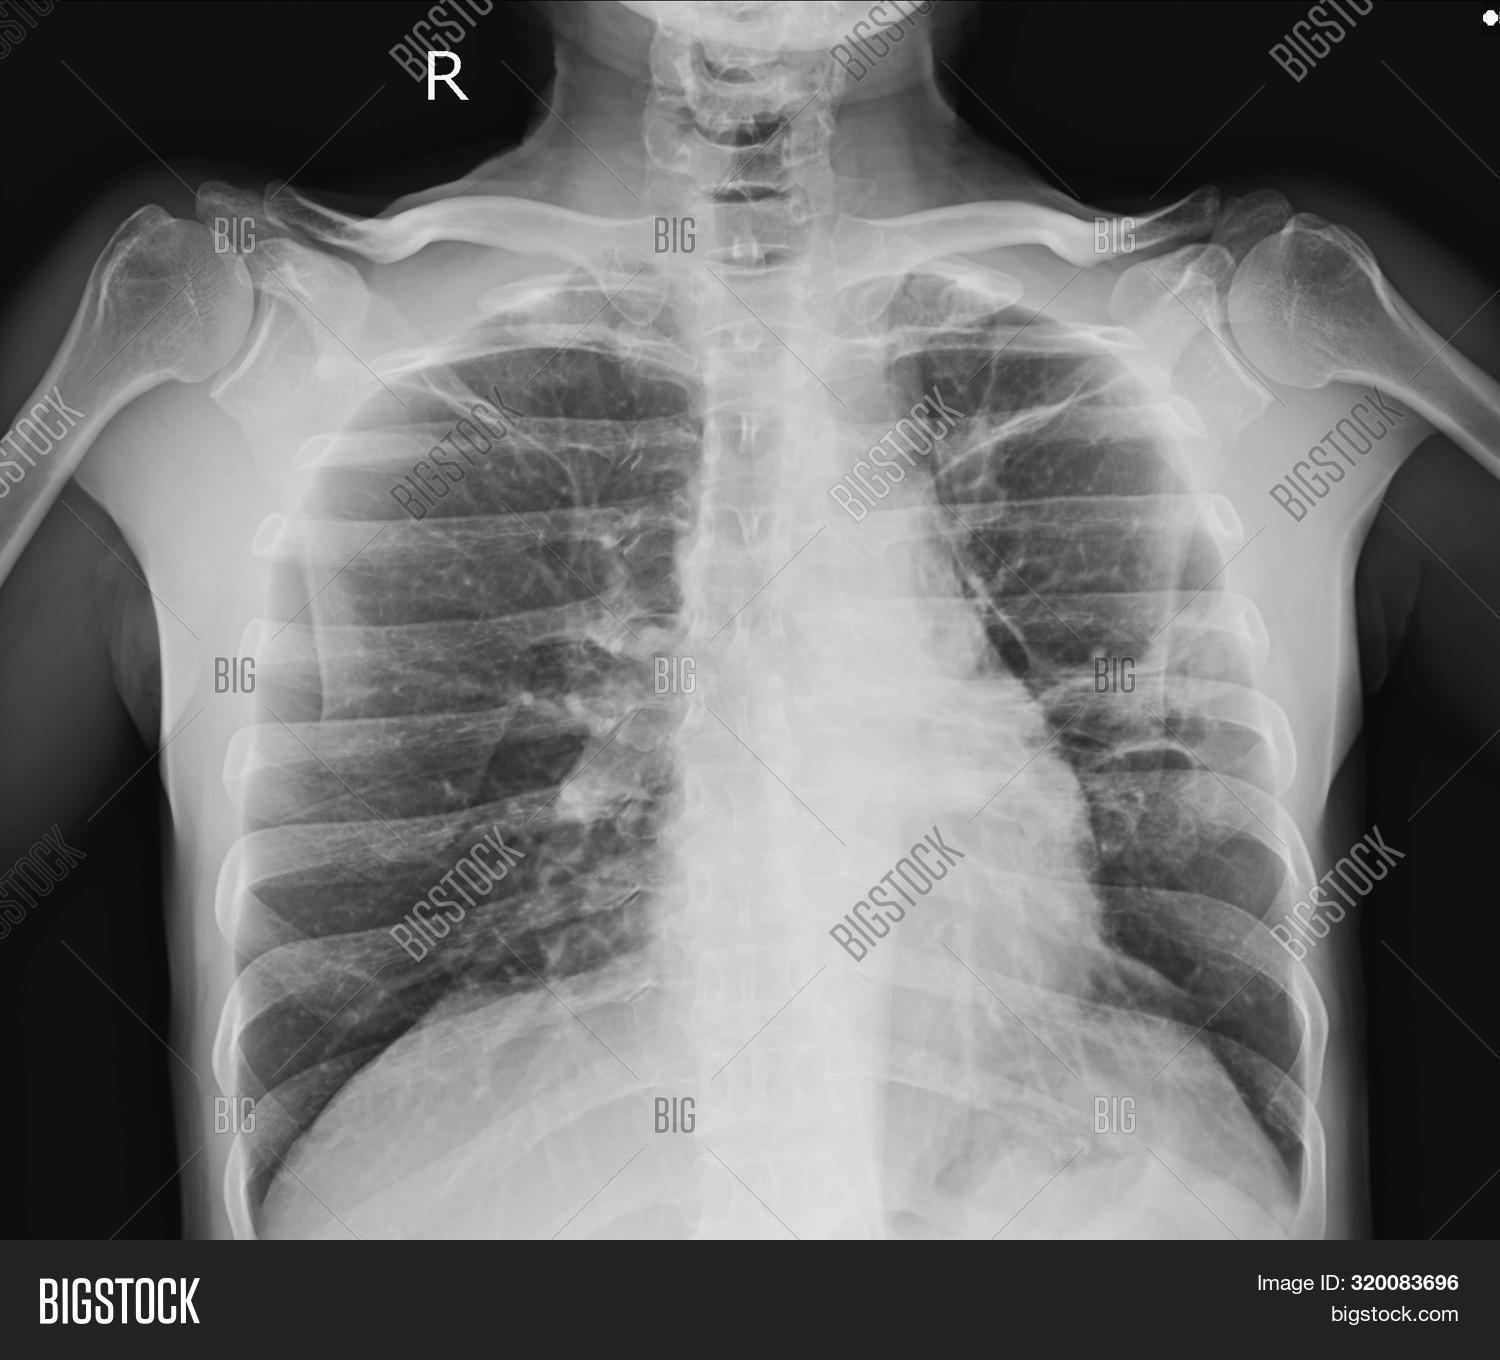

Pacemaker Xray Image Image & Photo (Free Trial) Bigstock Pacemaker And Panoramic X Ray there are two types of cardiac conduction devices (ccd's): The purpose of this article is to review the normal and abnormal radiographic appearances of cardiac pacemaker and implantable cardioverter defibrillator systems. Pacemakers and automatic implantable cardioverter. there are two major types of cardiac conduction devices: the dental literature also included articles regarding electromagnetic interferences to pacemakers, due. Pacemaker And Panoramic X Ray.